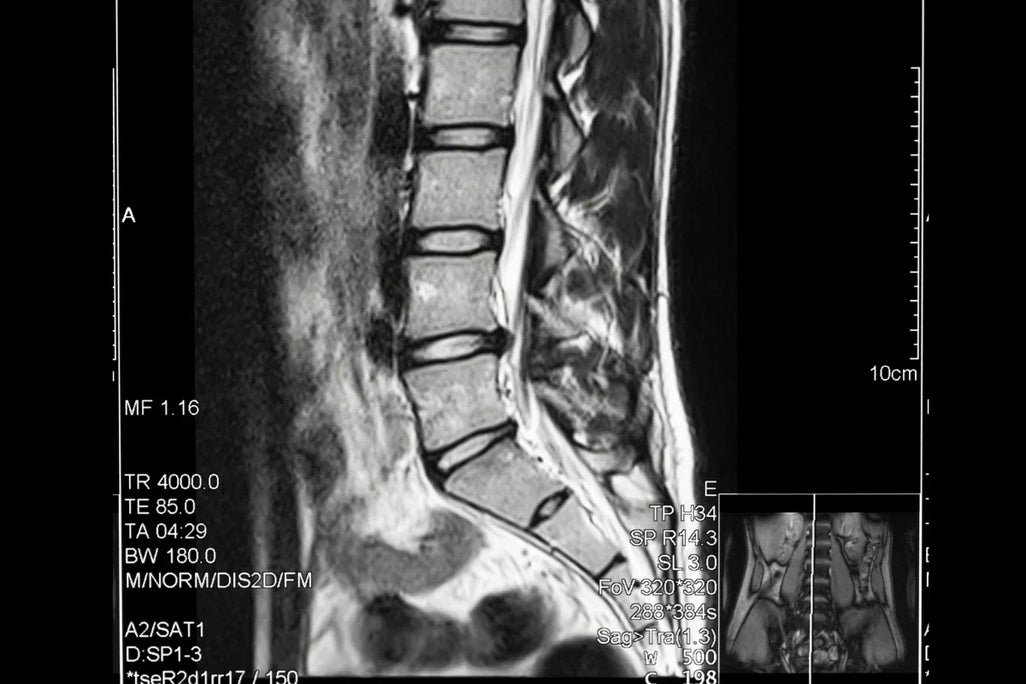

In a quiet consultation room several years ago, Mdm Chow received news that would reshape her immediate future: her L4-L5 vertebrae were compressing spinal nerves severely enough that surgery was becoming the recommended next step.

"I have very sharp pain in the spine between L4 and L5," she explains. "Pressing on the nerve. They want me to go for surgery. But it is high risk."

Structural vs. symptomatic outcomes: Imaging showed no change in the underlying spinal condition, yet clinical presentation improved dramatically. This suggests effective pain management without structural resolution may be sufficient for patient quality of life.